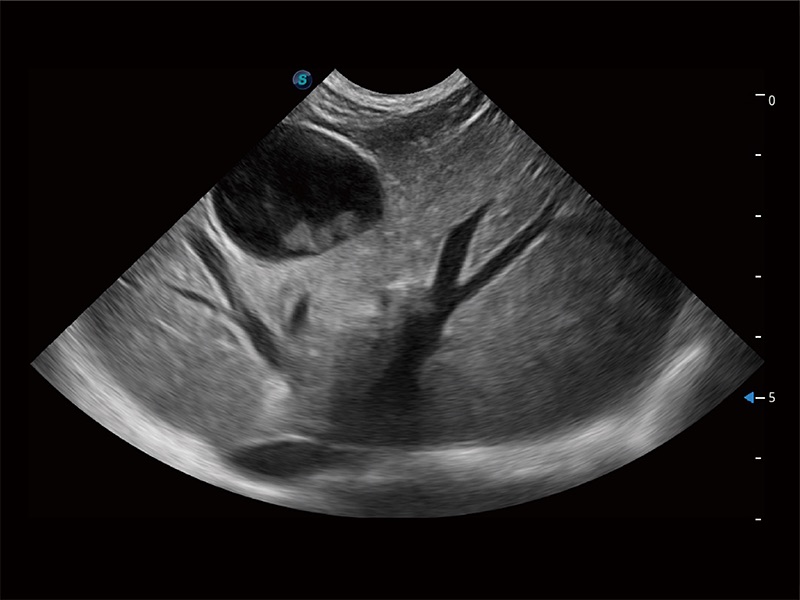

极大提升超低速微细血流的检出能力,同时更精准地滤除软组织和超声信号,为兽用医生提供以往无法通过常规血流获得的疾病诊断信息。